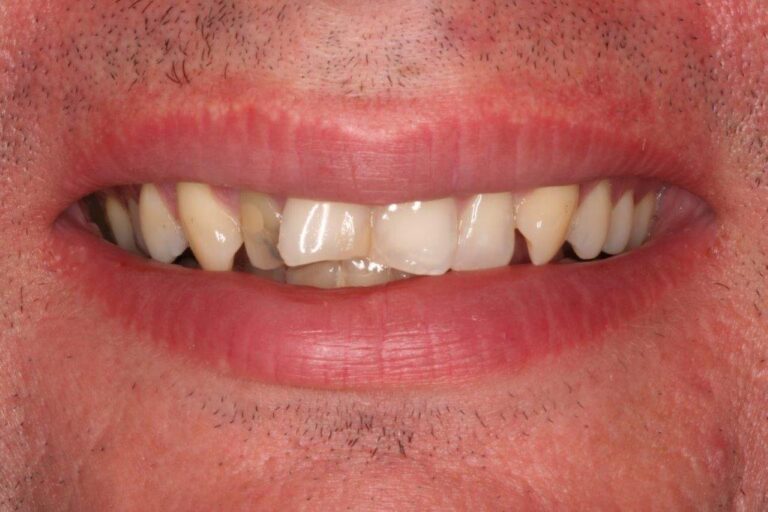

View Angle: front

Before